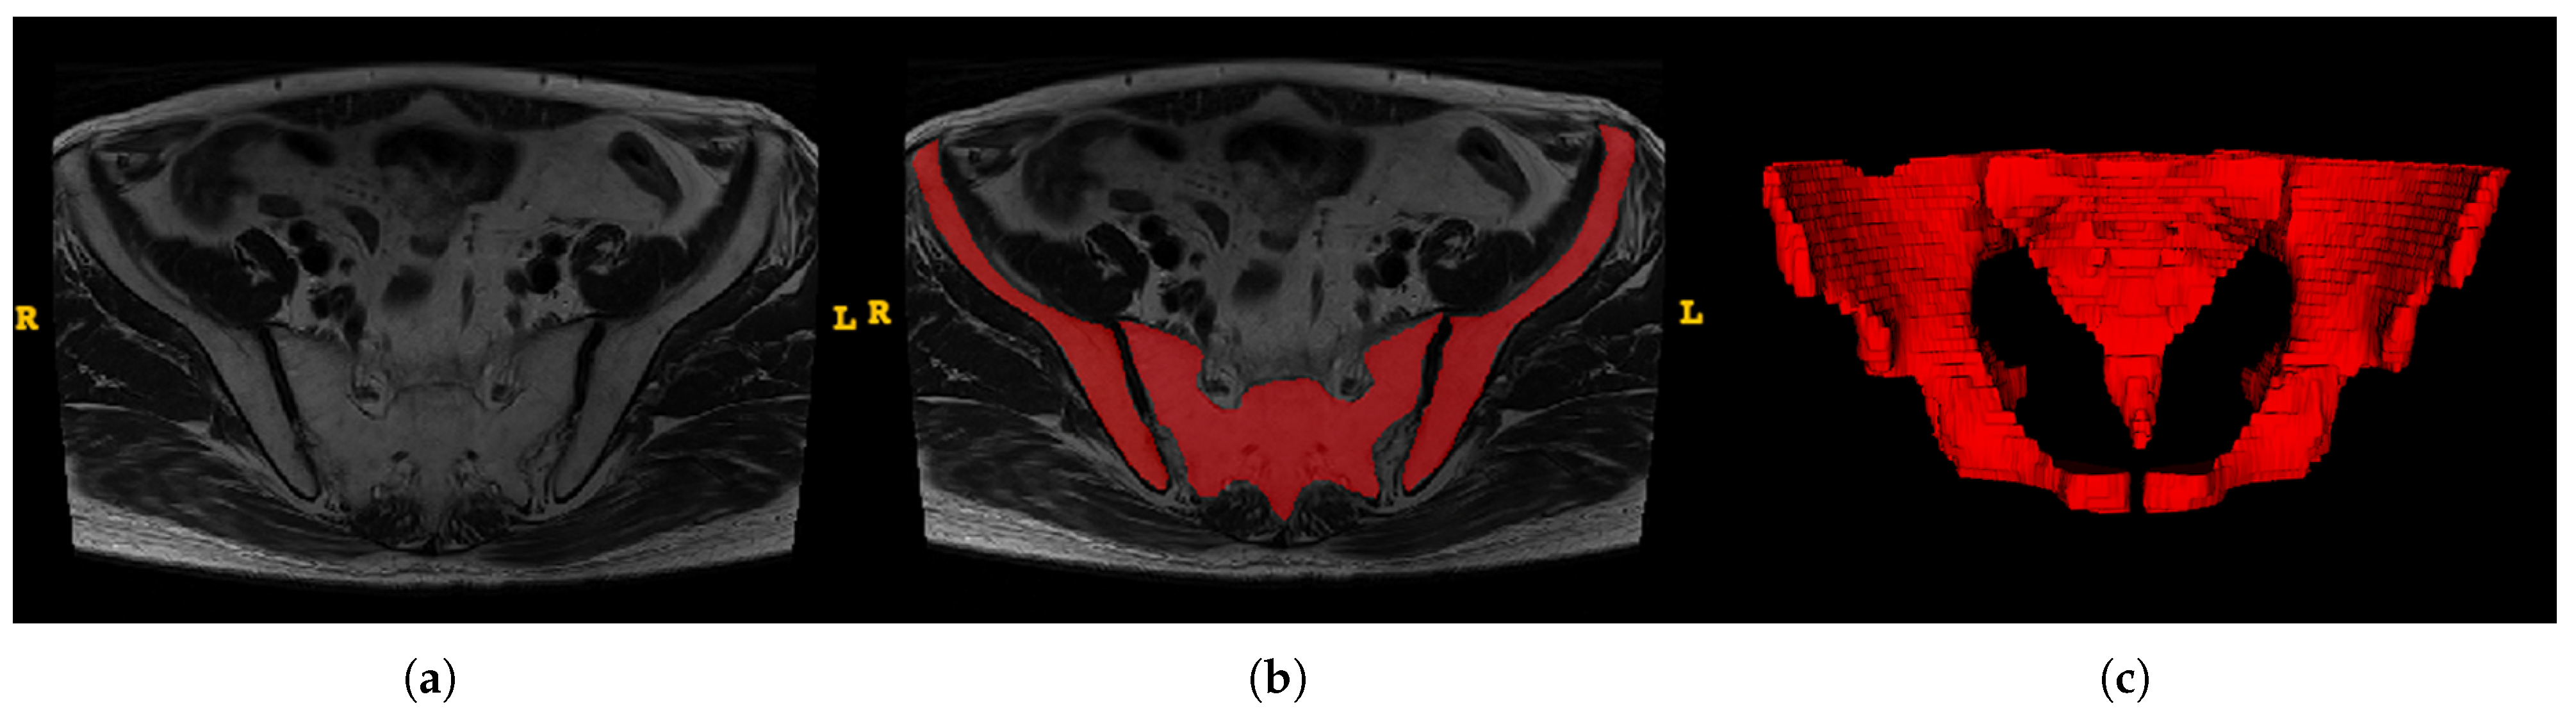

ITK-SNAP software (version 3.8.0, www.itksnap.org) was utilized to obtain the region of interest (ROI) for further analysis [16]. The ROIs were carefully delineated along with the pelvis (Figure 3). Two trained surgeons (Z.S., W.Y.H.) independently conducted segmentation, and two experienced radiologists (J.J.L., H.D.X.) were introduced for supervision.

Figure 3.

An example of manual segmentation of pelvis in MRI. (a) Bilateral ilium and sacrococcyx in T2-weighted images; (b) Manual segmentation on the same axial slice (Bilateral ilium and sacrococcyx are highlighted in red); (c) reconstruction of the pelvis.

To normalize the different scan settings between MR images of patients, the images and annotations were resampled to 1.5 mm×1.5 mm×1.5 mm voxel spacing using the SimpleITK library [17,18], and were then converted to the Neuroimaging Informatics Technology Initiative (NIfTI) format. To avoid the interference of the grayscale texture and irrelevant tissue, and for the the neural network model to pay attention to the bone structure and pelvic distance within the ROI, we set the voxel value to 0 for the non-ROI area, and to 1 for the bilateral ilium and the sacrococcyx. All images are padded to the same size, with a value of 0.